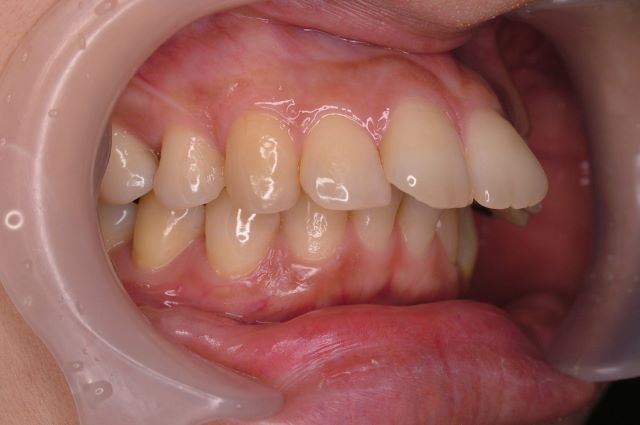

治療前

治療後

女性の患者様で、歯を可愛らしく小さくして欲しいというご要望でした。また、少しだけ白くしたいとのことで、そのような歯と歯並びを作り上げました。